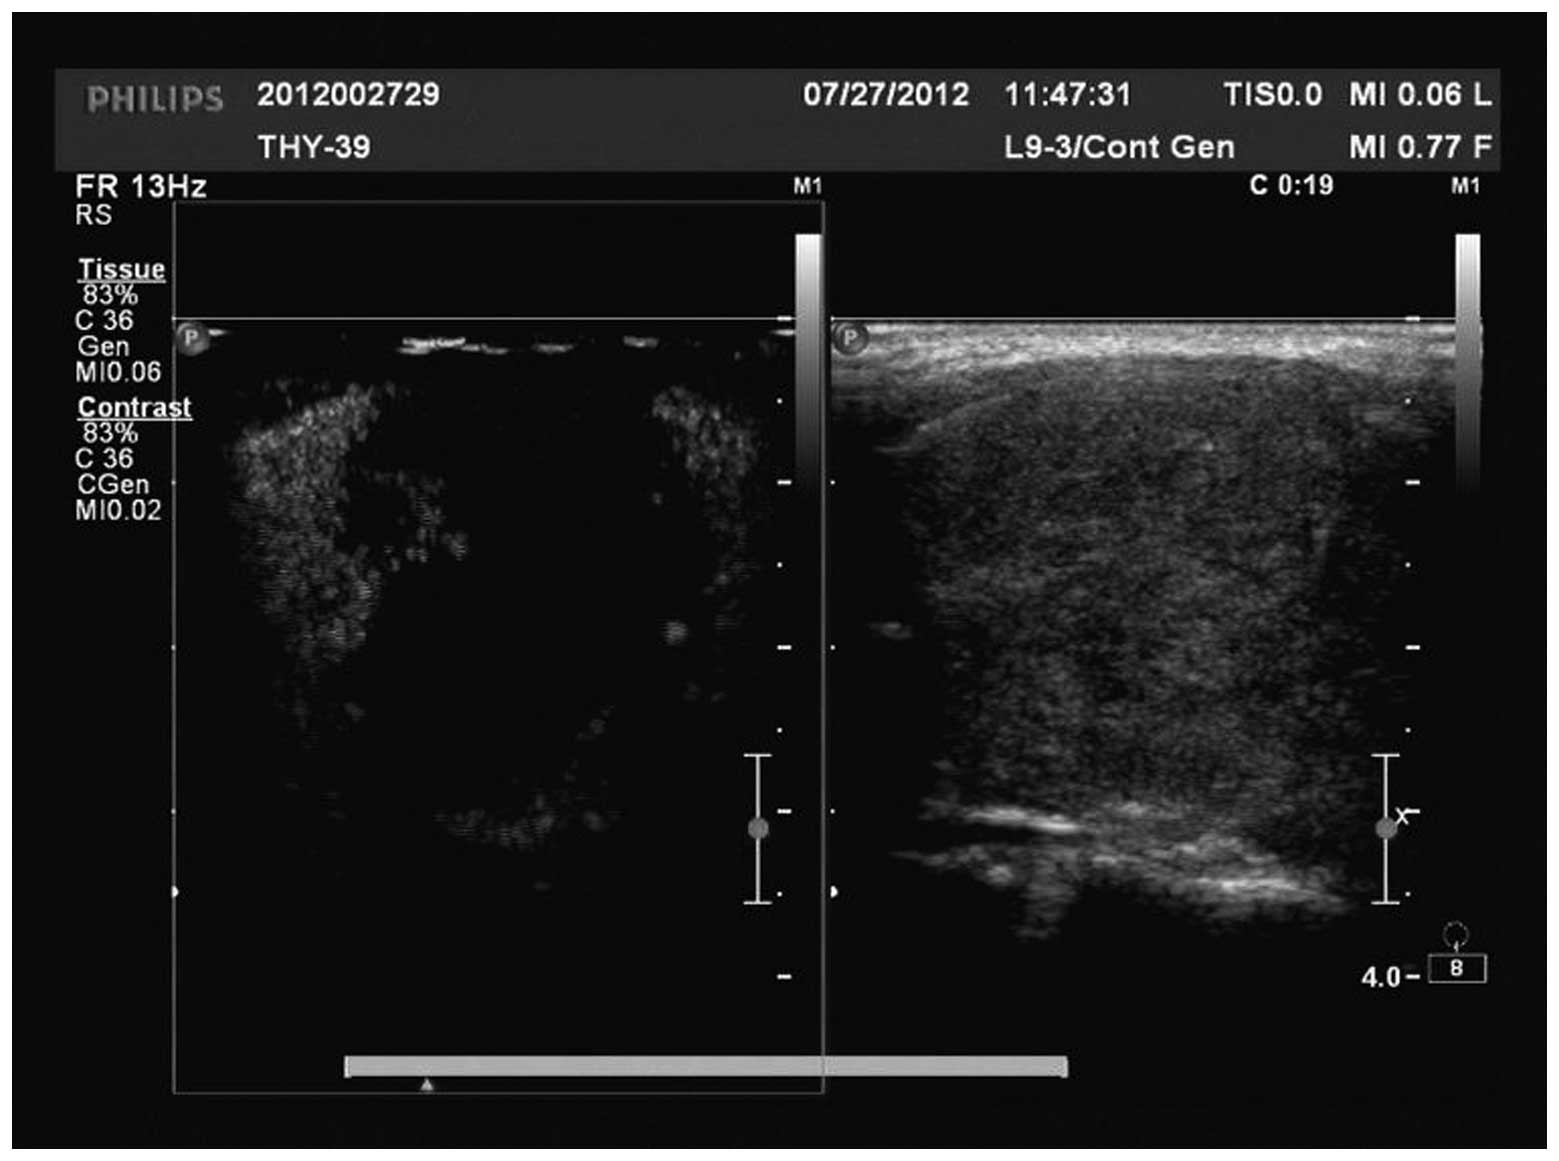

There were three types of manifestation, including irregular weak concentric ring enhancement (Fig. 1), no or weak enhancement (Fig. 2) and uneven enhancement (Fig. 3) in the CEUS images of the 51 nodules in 48 patients. All nodules provided adequate specimens and the satisfaction rate of tissue drawing was 100%. Of the 51 nodules, 44 (86.3%), five (9.8%) and two (3.9%) nodules were pathologically diagnosed as PTC, nodular goiter and focal Hashimoto’s disease, respectively. From the 44 nodules diagnosed as PTC, 43 (97.7%) and 34 (77.3%) nodules were detected by CEUS and conventional ultrasound, respectively, with a significant difference between the two methods (P=0.022). Eleven (25%) nodules were independently detected by CEUS and 31 (70.5%) nodules were detected by CEUS and conventional ultrasound. Only one nodule was not detected (2.3%).

Figure 3

Uneven enhancement by CEUS (pathologically diagnosed as PTC). CEUS, contrast-enhanced ultrasonography; PTC, papillary thyroid carcinoma.